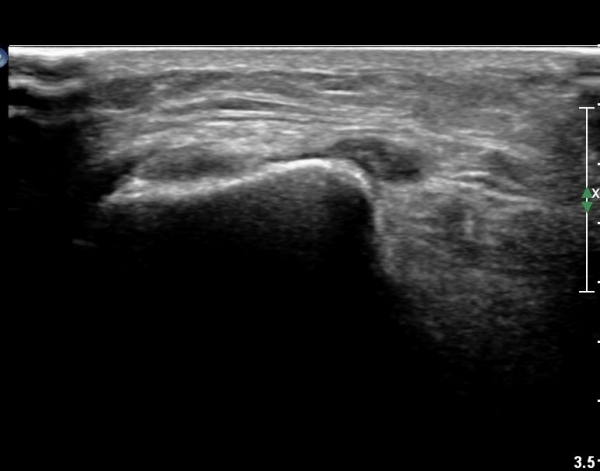

¹«¸­ ¿À±Ý ºÎÀ§ Ⱦ´Ü¸é°Ë»ç¿¡¼­ °æ°ñµ¿¸Æ Ç¥Ãþ¿¡ ºñ°ñ½Å°æ°ú °æ°ñ½Å°æÀÌ ºÐ¸®µÇ¾î °üÂûµÈ´Ù(»çÁø 1).